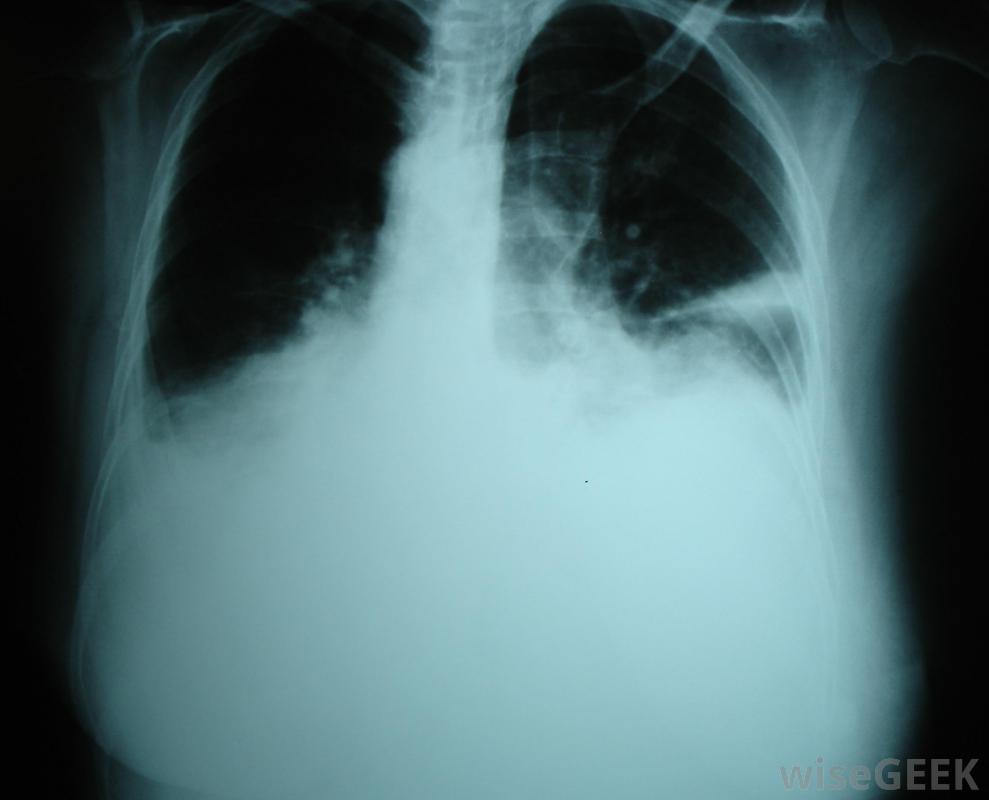

胸腔積液是胸腔內多余液體的積聚,胸腔包圍著肺部。正常情況下,胸膜中含有一層薄薄的液體,以保持肺部在呼吸過程中的平穩運動。當有過多液體時,右側胸腔積液發生在右側胸膜中,右側胸腔積液比左側胸腔積液更容易導致充血性心力衰竭胸腔積液。右側胸腔積液或右側胸腔積液的發生,是一種潛在疾病的結果。右側和左側胸腔的液位通常不同,稱為非對稱性胸腔積液。胸腔積液也可孤立于其中一個空洞,稱為單側胸腔積液。右胸腔積液主要與充血性心力衰竭(CHF)有關胸腔積液是胸腔積液在肺部周圍胸腔中的積聚。胸腔積液的最初癥狀通常是當胸腔中的液體達到一定量時大約500毫升。報告的癥狀包括呼吸困難或疼痛,以及呼吸時胸壁的運動減弱。當胸部和背部被交叉或輕拍時,共振也會減少當用聽診器檢查時,呼吸音可能會很遲鈍,也可能會有不尋常的聲音,如噼啪聲或摩擦聲,這是由于過多的液體產生的摩擦造成的。如果懷疑這些癥狀,通常會進行x光或超聲波檢查以確認診斷右胸腔積液主要與充血性心力衰竭相關。一旦診斷出右胸腔積液或左胸腔積液,則將一根大針放在背部或胸部取出,這一過程被稱為胸腔穿刺術。然后對液體進行分析,以確定液體的成分,以及液體是否滲出或滲出。滲出液表明是全身性的,其中身體的一部分,通常是心臟、肝臟或腎臟,會造成體內液體的整體失衡。滲出液表明肺部或周圍有問題,如細菌或病毒感染、栓塞或癌癥,需要進一步的檢查才能確診。還有其他類型的原因沒有分類,例如自身免疫性疾病和手術引起的積液,但這些并不常見。某些心臟疾病,如右胸腔積液,可以用超聲波檢測出來任何類型的胸腔積液的治療都是基于根本原因,必須治療才能解決整個問題。為了減少胸腔積液,會用針頭將多余的液體抽出。當積液較多時,可以使用引流管或進行手術。其他治療方法包括使用化學藥品治療感染和手術融合胸膜腔以阻止液體積聚。過去,結核是導致胸腔積液的主要原因。任何類型的胸腔積液的治療大多基于潛在原因醫生將傾聽患者的肺部,以診斷右胸腔積液。